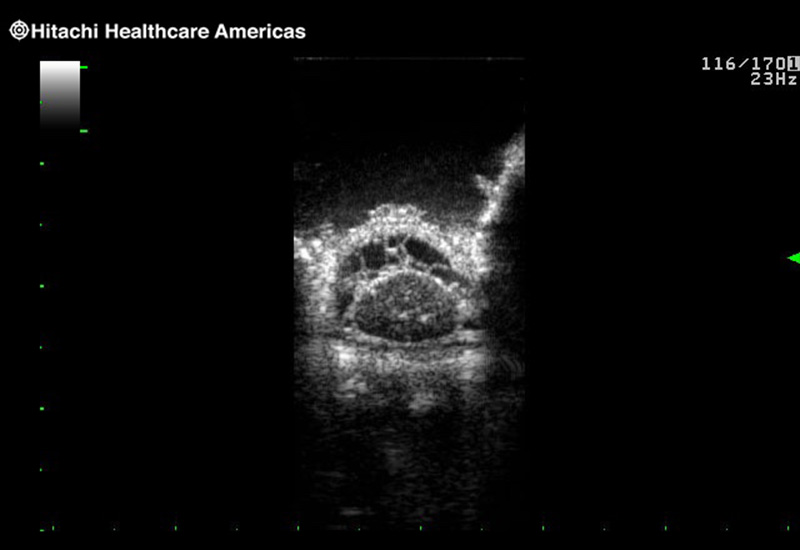

Superior guidance for all applications

Fujifilm Healthcare Americas is committed to designing tools that help surgeons navigate inside the human body and provide the necessary information to immediately make critical surgical decisions.

Fujifilm Healthcare's dedication to Surgeons provides outstanding ultrasound technology, professional support and the specialized tools necessary to best perform comprehensive real-time ultrasound imaging in Breast Surgery, General Surgery, Laparoscopic Surgery, Neurosurgery, Robotic Surgery and Surgical Oncology.

Imaging Clearly Defined

State-of-the-art digital architecture and advanced imaging features to redefine the capabilities of surgical ultrasound.